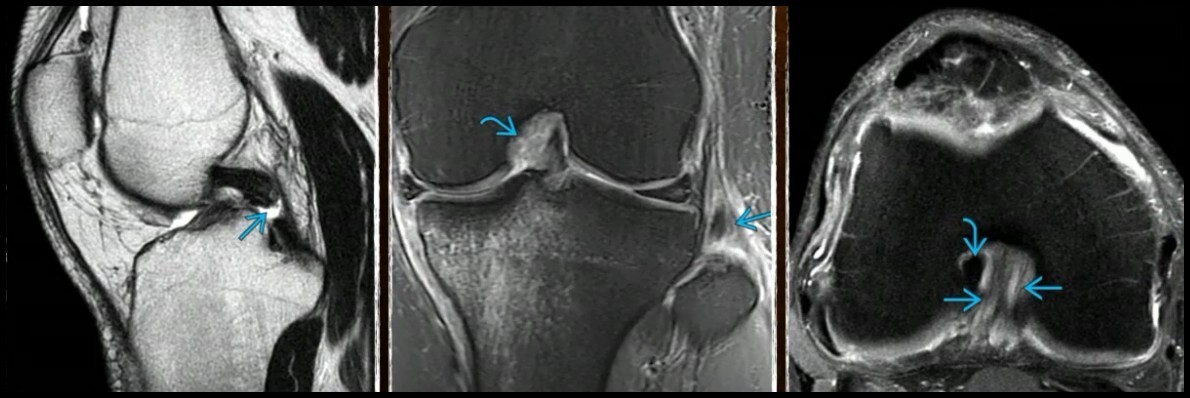

RNM (3)

• Especificidade e sensibilidade até 100%

• Descontinuidade no corte sagital

• Hipersinal em T2 (Inflamação)